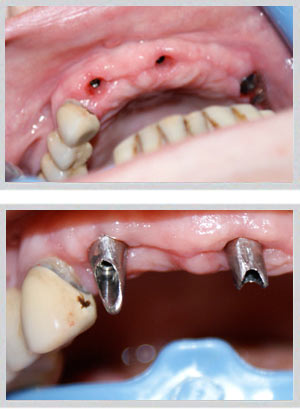

Multiple teeth dental implants Beirut Lebanon by Dr. Habib Zarifeh

Implant supported bridge multiple teeth Beirut Lebanon